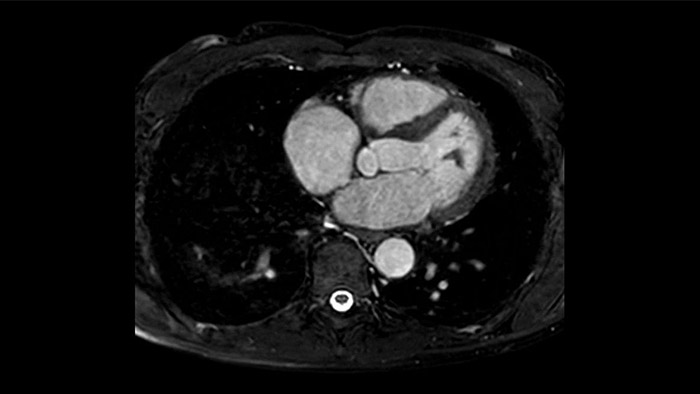

A utilidade do diagnóstico e prognóstico da RM cardíaca está a aumentar. Avalie a anatomia e função do coração utilizando aquisições cine, adquira informações sobre a perfusão e viabilidade do tecido cardíaco, visualize potenciais edemas com sequência de sangue escuro, aceda e quantifique mesmo a caracterização do tecido com a CardiacQuant.